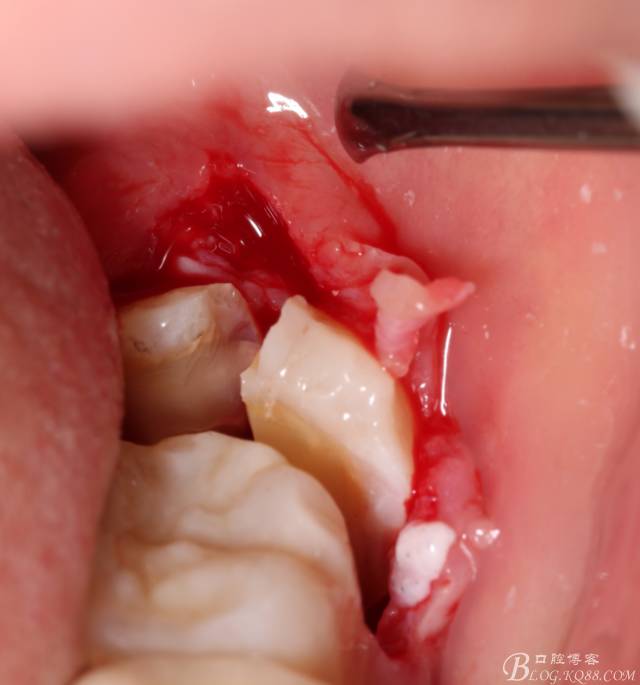

計(jì)劃總趕不上變化,何況是充滿變異的智齒。由于可操作空間較小,原來(lái)計(jì)劃?rùn)M向分根改成矢狀分根。

現(xiàn)在都在提倡微創(chuàng),個(gè)人看法微創(chuàng)是相對(duì),所當(dāng)然微創(chuàng)是我們的追求。完全撥出,縫合關(guān)閉創(chuàng)口,常規(guī)智齒撥除醫(yī)囑,不適隨診。